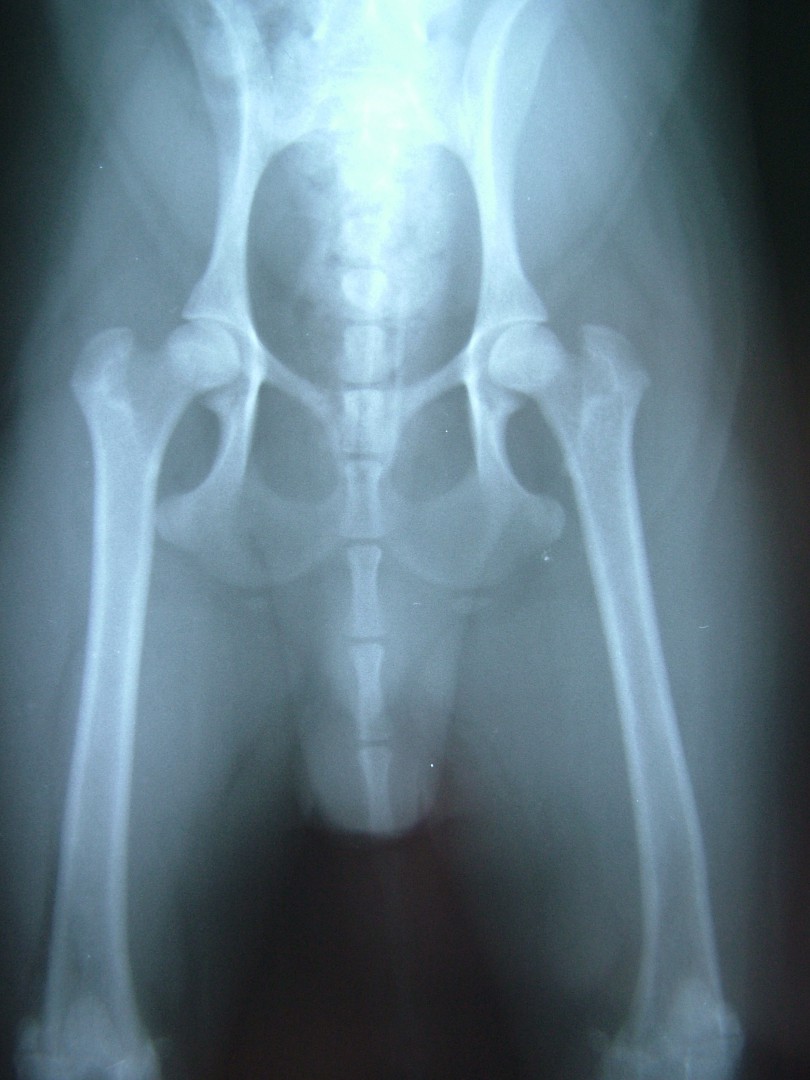

A röntgen felvétellel egyértelműen diagnosztizált betegség műtéti ellátást igényel. A beavatkozás során az elhalt combcsontfejet eltávolítjuk, megszűntetve az ízületi fájdalmat. A gyógyulási folyamat során a csípőízület helyén egy laza kötőszövetes kapcsolat alakul ki (álízület, pseudoarticulatio), mely fájdalommentes mozgást biztosít a medencecsont és a combcsont között.

A műtétet követő időszakban - a varratszedés idejéig - az állat szigorú mozgáskorlátozását írjuk elő. Ezt követően a fokozatosság elvét betartva folyamatosan, először csak pórázon, majd szabadon jártatjuk, majd futtatjuk a beteget a műtétet követő 4 héten át.A betegek szinte minden esetben tünetmentesen gyógyulnak.